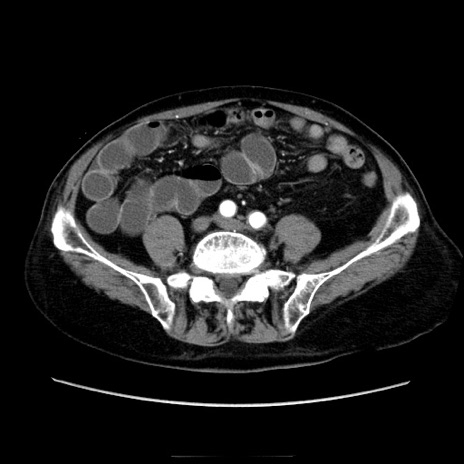

症例21(横断像)

【症例】70歳代男性

【主訴】腹痛

【現病歴】肝硬変・肝細胞癌にてかかりつけの方。約9時間前に食後より腹痛出現。症状が徐々に増悪し、嘔吐出現したため来院。

【既往歴】肝硬変、肝細胞癌(RFA、TACE後)

【身体所見】意識清明、表情苦悶様、BT 36℃、BP 129/78mmHg、P 88bpm、SpO2 97%(RA)、右上腹部から心窩部にかけて圧痛あり、反跳痛なし、筋性防御あり。

【データ】WBC 5800、CRP 0.16